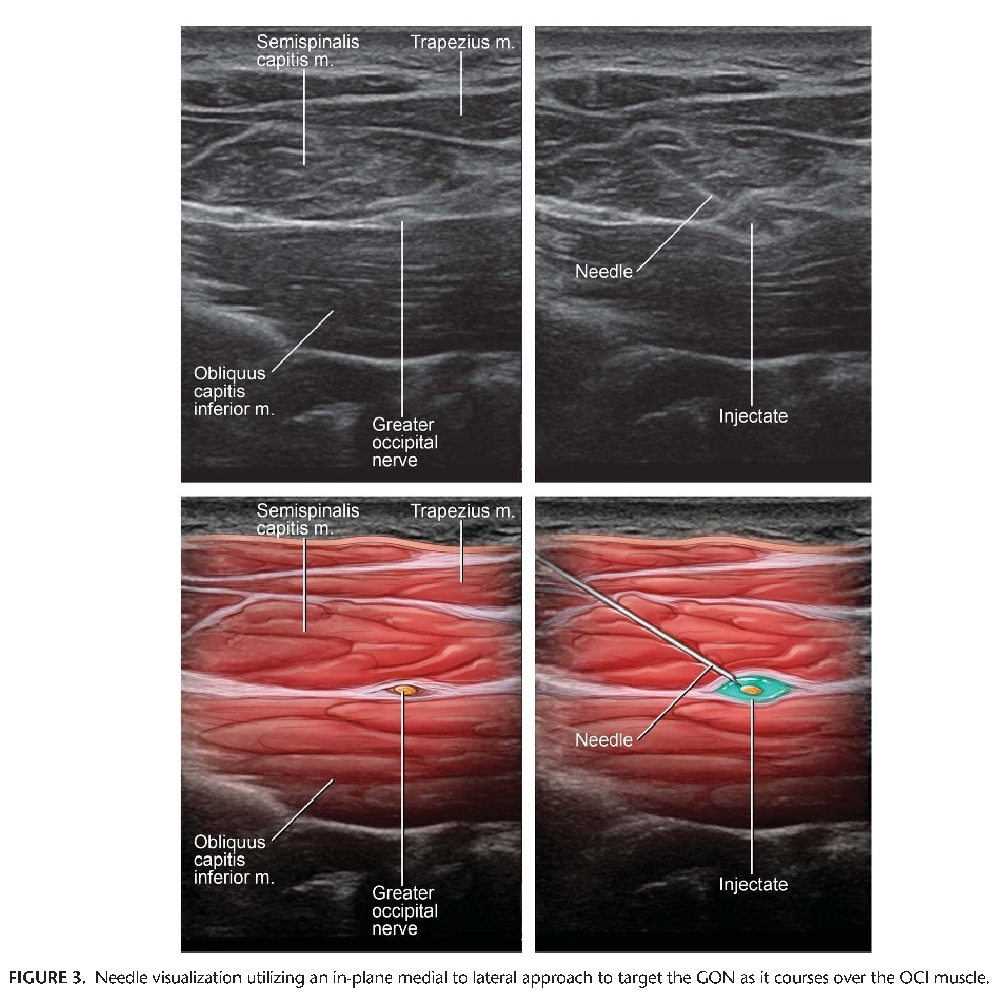

Prior to inserting the needle, use Doppler to identify the relevant vasculature, because the vertebral artery is frequently located deep to the obliquus capitis inferior muscle and laterally to the GON.[4] After proper visualization of relevant anatomy, Pingree et al described inserting a 25-gauge, 2-inch spinal needle in plane with the transducer from medial to lateral, as depicted in Figure 3.[5] Different combinations of local anesthetic and steroids may be injected. Pingree et al used a total of 4 cc (1 cc of 2% lidocaine, 2.5 cc of 0.25% bupivacaine, and 3 mg of betamethasone) with good results.[5] Visualizing the needle tip during insertion is of the utmost importance because the block is performed in relative close proximity to both the vertebral artery and the spinal cord. Local anesthetic spread around the GON during injection is also important to performing the block safely and effectively.